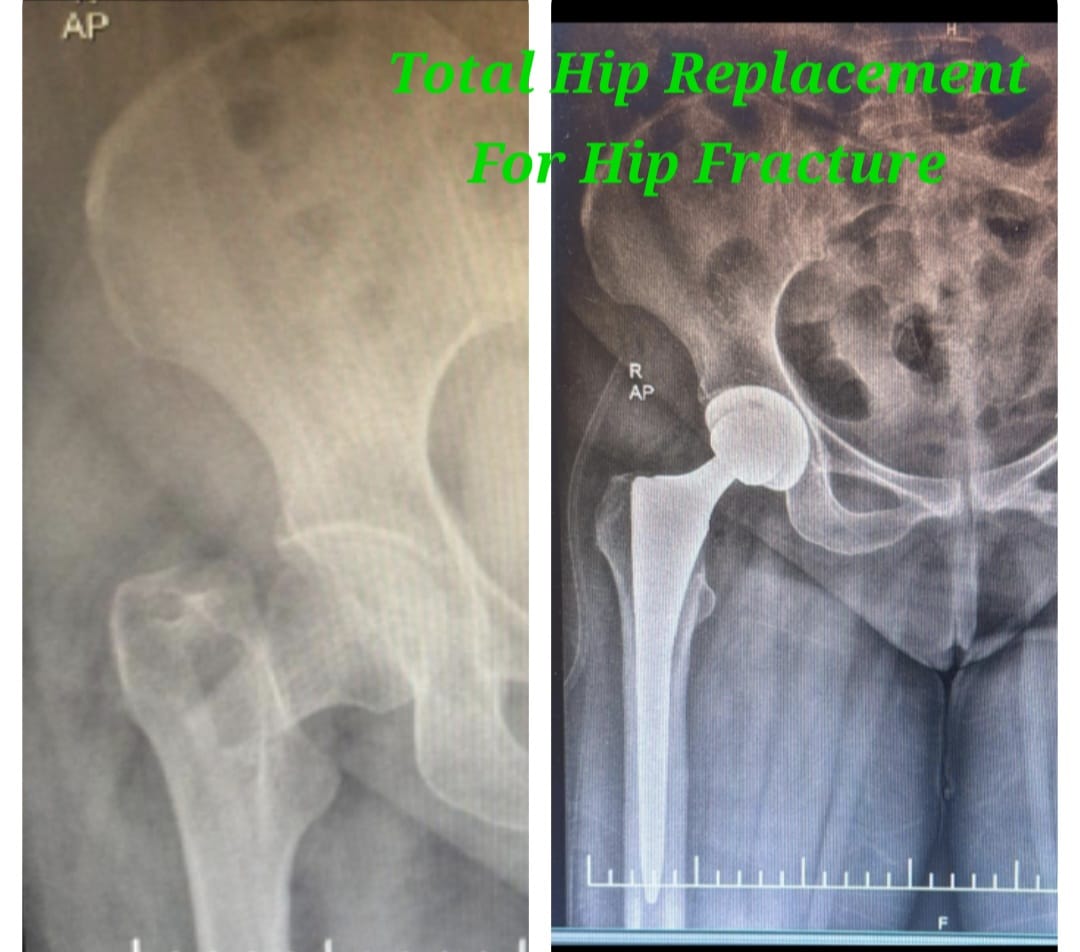

Primary total hip replacement is a definitive surgical procedure performed to relieve severe hip pain and restore joint mobility in patients suffering from advanced hip arthritis, fractures, avascular necrosis, or extensive joint damage. The procedure involves replacing the damaged hip joint surfaces with high-quality artificial implants designed to provide smooth, stable, and pain-free movement.

This surgery is recommended when conservative treatments such as medications, injections, physiotherapy, and lifestyle modifications fail to provide lasting relief. Careful preoperative planning and modern surgical techniques ensure accurate implant positioning, optimal joint alignment, and long-term durability.